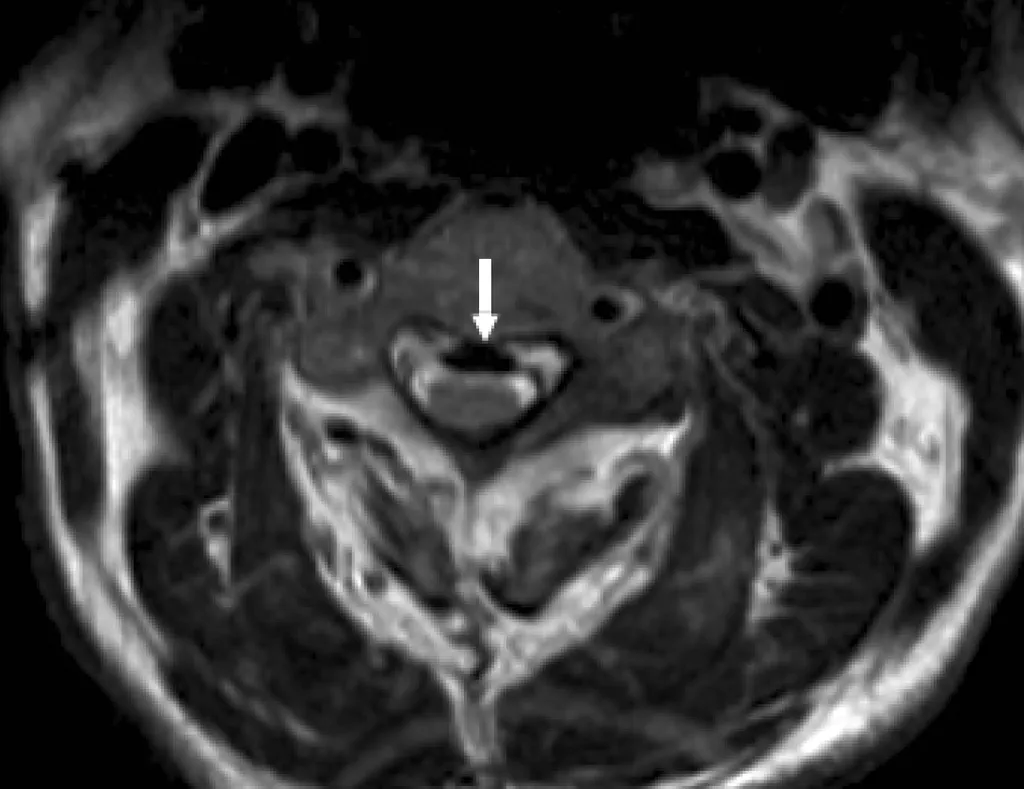

【107-1 醫學(六) 第72題】71歲男性不慎跌倒之後,頸部異常疼痛,合併有上肢酸麻感覺;磁振掃描橫向T2加權影像如附圖。其最可能的診斷為何?

這張頸椎橫向T2加權磁振掃描影像顯示脊髓前方有一個明顯的低訊號(黑色)硬化結構,壓迫到脊髓,這是後縱韌帶骨化 (OPLL) 的典型表現。